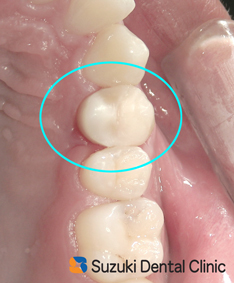

オールセラミック 神経 守る 施術から2週後、痛みや腫れがないことを確認できました。次は、この歯に「被せ物を装着する」準備です。様々な被せ物の種類、特徴を説明した結果、「オールセラミックの被せ物」を選択されました。理由は、熱を伝えにくく(神経への刺激が少ない)、強度もあり、審美性(銀色と白色の違い)にも優れているからです。セラミックの装着が終わってから、現在1ヶ月ほどが経ちました=写真。歯茎はきれいに回復し、歯の神経を抜くこともなく、落ち着いています。このまま、順調に経過してくれることを期待します。